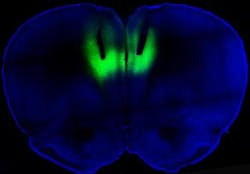

To test whether altering the activity in this brain region could impact addiction, Chen and his colleagues employed optogenetics to shut the activity on and off using a laser. First, they took light-sensitive proteins called rhodopsins and used genetic engineering to insert them into neurons in the rat's prefrontal cortex. Activating this region with a laser tuned to the rhodopsins turned the nerve cells on and off. Turning on these cells wiped out the compulsive behavior, while switching them off turned the non-addicted ones into addicted, the researchers found.